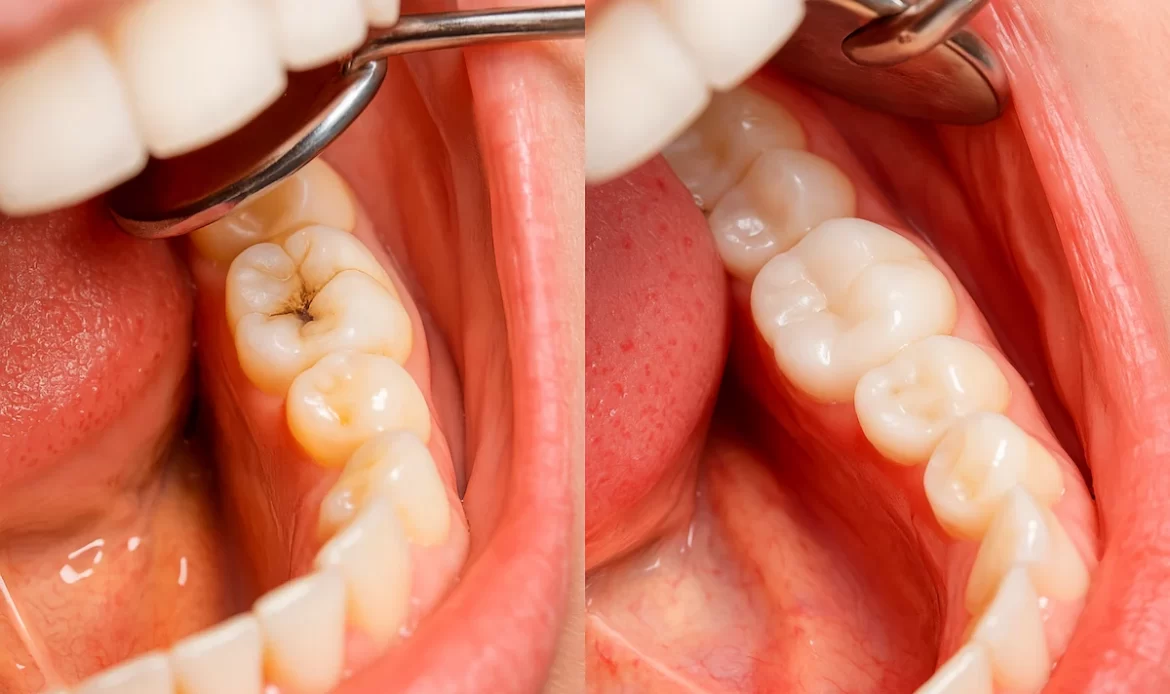

Détartrage, plombages blancs et traitements pour préserver vos dents naturelles.